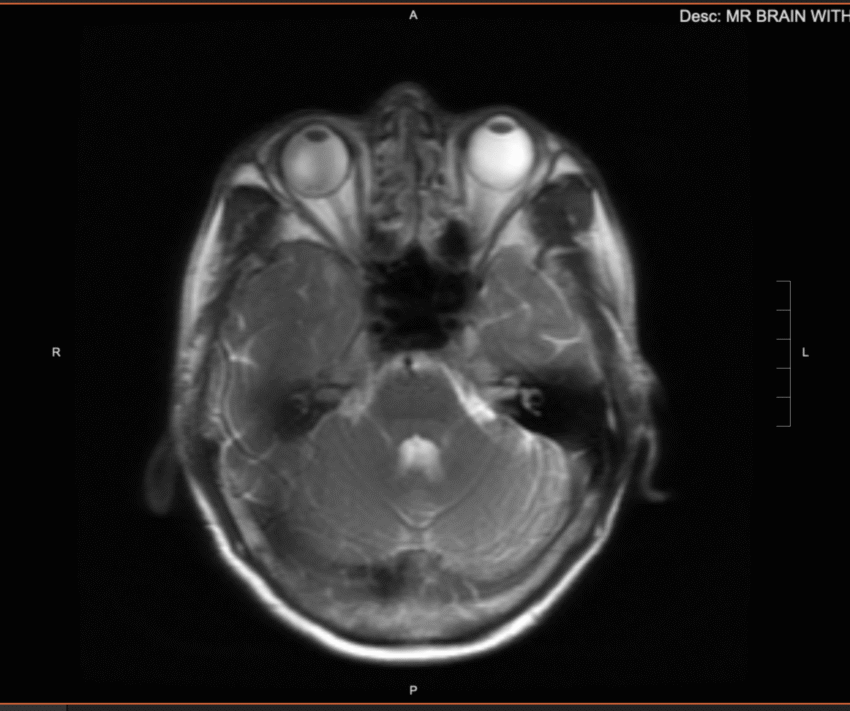

I got the results back from an MRI scan I had done a couple of weeks ago at UCSF, as part of a long COVID study I’m participating in. I don’t have the knowledge to interpret the findings, but the scans of my brain are pretty fascinating to look at.

It’s hard to believe that every memory, every experience, every bit of knowledge I have acquired, is all contained in this vessel.